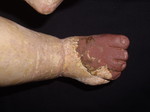

Echa un vistazo a esta galería de arte virtual en la que se pueden ver algunas de las restauraciones que he hecho. Quizá descubras algo que te interese durante la visita... o pienses en alguna obra de arte que sepas que está algo deteriorada, para que te hagas una idea de cómo podría quedar si se pone en buenas manos.